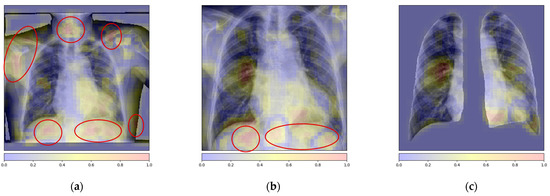

Attention-Based Local Feature Extraction

5. Discussion